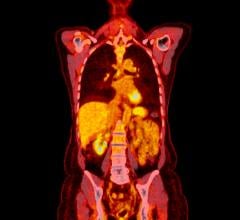

The multicenter, international study analyzed PSMA PET scans of nearly 2,000 patients with prostate cancer and rising PSA levels. Patterns of disease spread on PSMA PET imaging were used to classify prostate cancer patients into both low- and high-risk groups. High-risk groups were found to have higher rates of metastatic disease on PSMA PET compared to low-risk groups. However, PSMA PET also found metastatic disease in low-risk and no disease in high-risk patients.

“Our study underscores the utility of the EAU risk groups to determine risk of metastasis in biochemically recurrent prostate cancer. But not every high-risk patient has metastases and not every low-risk patient has locoregional or no disease,” said Wolfgang Fendler, MD, nuclear medicine physician at University Hospital in Essen.

He continued, “The ultimate aim of imaging is to provide the right treatment for each patient. As evidenced in this research, the accuracy of PSMA PET is essential to improve stratification and potentially outcomes both in low-risk and high-risk settings.”